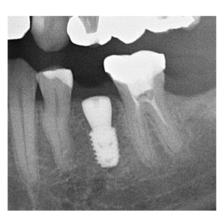

―症例集―

症例一覧